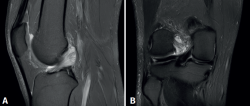

Figura 3. Visión artroscópica desde el portal anterolateral de la rodilla derecha. Se observa el quiste sinovial del ligamento cruzado anterior (LCA) en el fascículo posterolateral. A: visión con palpador diferenciando fibras del LCA sano del quiste; B: visión con la rodilla en posición “de cuatro” en la que se observa el pinzamiento del quiste en el espacio tibiofemoral lateral.

En ambos pacientes se realizó anestesia raquídea para realizar la cirugía y se utilizó manguito de isquemia a nivel del muslo. Se colocó al paciente en decúbito supino, utilizando un soporte en U en el tercio distal del muslo para la fijación de la extremidad. Se realizaron los portales artroscópicos habituales anterolateral y anteromedial, objetivando en la exploración diagnóstica de la rodilla la presencia de un ganglión localizado en el fascículo posterolateral del LCA (Figura 3) que, cuando se realizaban los movimientos de flexión y en posición de cuatro, se pinzaba en el espacio articular tibiofemoral externo. Para realizar la resección artroscópica del quiste se colocó al paciente en la posición “de cuatro”, facilitando la diferenciación anatómica de los fascículos anteromedial y posterolateral del LCA, tal y como proponen Hopper G et al.(4). Se realizó la disección y exéresis cuidadosa del quiste con una pinza basket, un terminal shaver de 4 mm y un terminal de ablación por radiofrecuencia (Figura 4). Al finalizar la resección del quiste, se realizó una nueva exploración dinámica de la rodilla, donde se evidenció la ausencia de pinzamiento entre el LCA, el cóndilo femoral y el platillo tibial lateral, a la vez que se comprobó la estabilidad del remanente del LCA (Figura 5).